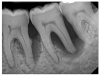

(7.) Progressive improvement in bone quality, quantity, and morphology during each time period, especially in the furcation area of tooth No. 18, which shows a noticeable narrowing of the width of the bony defects, slight apical resorption of the distal root of tooth No. 18, and the encasing of residual cementum on the distal root of No. 19 by new bone formation. Periapical radiographs were taken of teeth Nos. 17, 18, and 19 on June 25, 2016, January 28, 2017, August 23, 2019, and September 4, 2020, respectively, the final of which was taken after almost 5 years post-initial scaling and root planing and alternating supportive periodontal maintenance.

(8.) Progressive improvement in bone quality, quantity, and morphology during each time period, especially in the furcation area of tooth No. 18, which shows a noticeable narrowing of the width of the bony defects, slight apical resorption of the distal root of tooth No. 18, and the encasing of residual cementum on the distal root of No. 19 by new bone formation. Periapical radiographs were taken of teeth Nos. 17, 18, and 19 on June 25, 2016, January 28, 2017, August 23, 2019, and September 4, 2020, respectively, the final of which was taken after almost 5 years post-initial scaling and root planing and alternating supportive periodontal maintenance.

Figure 8

(9.) Progressive improvement in bone quality, quantity, and morphology during each time period, especially in the furcation area of tooth No. 18, which shows a noticeable narrowing of the width of the bony defects, slight apical resorption of the distal root of tooth No. 18, and the encasing of residual cementum on the distal root of No. 19 by new bone formation. Periapical radiographs were taken of teeth Nos. 17, 18, and 19 on June 25, 2016, January 28, 2017, August 23, 2019, and September 4, 2020, respectively, the final of which was taken after almost 5 years post-initial scaling and root planing and alternating supportive periodontal maintenance.

Figure 9

(10.) Progressive improvement in bone quality, quantity, and morphology during each time period, especially in the furcation area of tooth No. 18, which shows a noticeable narrowing of the width of the bony defects, slight apical resorption of the distal root of tooth No. 18, and the encasing of residual cementum on the distal root of No. 19 by new bone formation. Periapical radiographs were taken of teeth Nos. 17, 18, and 19 on June 25, 2016, January 28, 2017, August 23, 2019, and September 4, 2020, respectively, the final of which was taken after almost 5 years post-initial scaling and root planing and alternating supportive periodontal maintenance.

Figure 10

The patient's periodontal disease improved with initial nonsurgical periodontal therapy that involved scaling and root planing. This initial treatment was followed by only SPT every 3 months. Despite treatment, residual deep periodontal probing depths remained, so a decision was made to maximize improvements with nonsurgical therapy and to reassess as needed to determine whether surgical intervention was appropriate. After almost 5 years of SPT and good patient compliance with plaque control and supportive care, the periodontium was stable. Because of the resulting bone formation and improvements in clinical attachment levels (Figure 7 through Figure 13), it was determined that periodontal surgical intervention was not necessary.

In the case report presented, treatment with nonsurgical therapy for 5 years effectively halted destruction and led to bone regeneration and improved clinical attachment levels. Although the primary etiology of periodontal disease is well documented, secondary etiologic and contributing factors are numerous.16 After initial therapy in the current case, there was radiographic evidence of a hypercementosis-like lesion on the distal root of tooth No. 19 (Figure 7 through Figure 10). Hypercementosis is a nidus for plaque accumulation leading to disease progression; however, the presence of this lesion did not explain the disease severity observed for tooth No. 18. Chronic periodontitis is the most widespread form of periodontal disease, and nonsurgical periodontal therapy is the most common type of therapy.17 Scaling and root planning is the gold standard for periodontal treatment. When performed meticulously, they result in improvement of clinical parameters through changes related to tissue shrinkage, long junctional epithelium, new attachment, and in rare circumstances, regeneration.18 The use of nonsurgical periodontal therapy for treatment of periodontal disease requires that the timing for re-evaluation is customized for each patient. Because individuals heal at different rates, the overall medical condition, nutritional intake, environmental and social risks factors, local factors, and colonization of pathogenic bacteria of patients should be considered.7,8 Some patients cannot afford, or choose not to pursue, surgical periodontal therapy. For these patients, clinicians should delay surgical decisions until periodontal risk factors are addressed and nonsurgical efforts are exhausted.